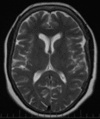

Response to treatment is not limited by variability in FHR. The vertical lines show the range in which the patients' FHR can vary while maintaining a GCS of 15. The X on each line represents each patients' baseline FHR. Poor compliance predisposes the patient to unsuccessful treatment. Patient 1 had an irreversibly floppy brain. Patient 2 had an abnormally stiff brain. Patient 3 had regained almost normal brain compliance. Patient 4 had regained his baseline brain stiffness. Abbreviations: FHR, frontal horn ratio; GCS, Glasgow Coma Score.References